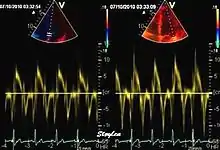

Tissue Doppler echocardiography (TDE) is a medical ultrasound technology, specifically a form of echocardiography that measures the velocity of the heart muscle (myocardium) through the phases of one or more heartbeats by the Doppler effect (frequency shift) of the reflected ultrasound. The technique is the same as for flow Doppler echocardiography measuring flow velocities. Tissue signals, however, have higher amplitude and lower velocities, and the signals are extracted by using different filter and gain settings. The terms tissue Doppler imaging (TDI) and tissue velocity imaging (TVI) are usually synonymous with TDE because echocardiography is the main use of tissue Doppler.

Like Doppler flow, tissue Doppler can be acquired both by spectral analysis (spectral density estimation) as pulsed Doppler[1] and by the autocorrelation technique as colour tissue Doppler[2] (duplex ultrasonography). While pulsed Doppler only acquires the velocity at one point at a time, colour Doppler can acquire simultaneous pixel velocity values across the whole imaging field. Pulsed Doppler on the other hand, is more robust against noise, as peak values are measured on top of the spectrum, and are unaffected of the presence of clutter (stationary reverberation noise).

Pulsed tissue Doppler echocardiography

This has become a major echocardiographic tool for assessment of both systolic and diastolic ventricular function. However, as this is a spectral technique, it is important to realise that measurement of peak values is dependent on the width of the spectrum, which again is a function of gain setting.

Pulsed wave spectral tissue Doppler has become a universal tool that is part of the general echocardiographic examination. Like any other echocardiographic measurement, measures by tissue Doppler should be interpreted in the context of the whole examination. The velocity curves are in general taken from the base of the mitral annulus at the insertion of the mitral leaflets, in the septal and lateral points of the four chamber view, and eventually the anterior and inferior points of the two-chamber views. For the right ventricle it is customary to use the lateral point of the tricuspid annulus only. Averaging peak velocities from the septal and lateral point has become common, although it has been shown that averaging all four points mentioned above, gives significantly less variability[3]

The method measures annular velocities to and from the probe during the heart cycle.

Annular velocities summarize the longitudinal contraction of the ventricle during systole, and elongation during diastole. Peak velocities are commonly used.